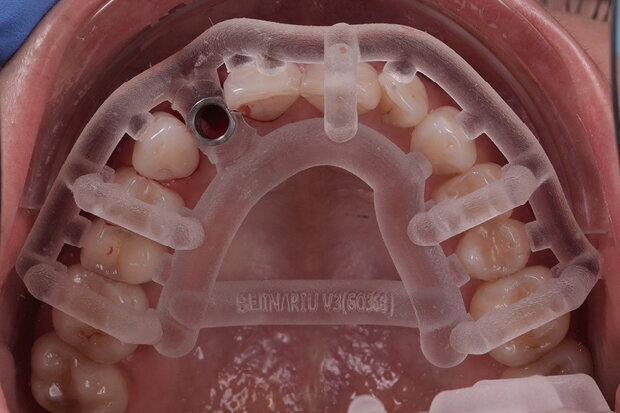

Fig. 7. Printed drill template (Mguide, MIS)

Fig. 10. Implant insertion (NP implant, MIS) with drill template

All the items required for the surgical intervention have been prepared and are now ready for use: This includes the printed drill template (Fig. 7) and the temporary implant restoration (Fig. 8). Tooth 12 is now extracted atraumatically in the “real world” (Fig. 9).

Immediately afterwards, the fit of the drill template is checked in the oral cavity and the implant is inserted according to the drill protocol (Fig. 10). This is followed by the augmentative measures planned in advance and finally, the temporary crown is screwed on (Figs 11 and 12).